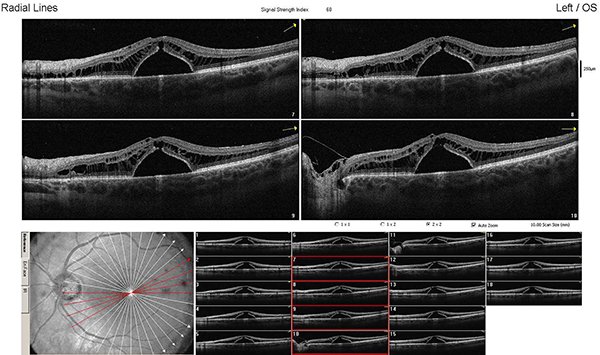

Al no presentar respuesta ante los tratamientos recibidos, reinterpretamos el cuadro clínico, observando detenidamente en el fondo de ojo derecho y en OCT una lesión compatible con foseta del disco óptico con filtración de líquido hacia el espacio subretinal (figs. 4 y 5).

Decidimos realizar tratamiento quirúrgico: vitrectomía por pars plana (VPP) con peeling de membrana limitante interna (PMLI) y aposición de flap sobre el pit, taponamiento con hexafluoruro de azufre y endofotocoagulación peripapilar (figs. 6 y 7).

Figura 4. Retinografía color de polo posterior derecho con alteración a nivel del margen temporal del disco óptico (flecha: pit de papila).

Figura 5. OCT de ojo derecho. En el nervio óptico, el espacio hiporreflectivo corresponde al pit de papila.

Examen oftalmológico postoperatorio mediato: AVMC OD 2/10, fondo de ojo derecho: pit de papila, atrofia peripapilar, fotocoagulación láser peripapilar y retina aplicada a nivel macular (figs. 8 y 9), y en OCT: retina aplicada con alteración de línea IS/OS (fig. 10).

Un mes después presentaba nuevamente disminución de la AV OD (1/10) y recidiva del desprendimiento seroso con retinosquisis en OCT. Mantuvimos conducta expectante y repetimos OCT a los siete días, donde observamos retina aplicada (fig. 11).

Realizamos imágenes de seguimiento, sin cambios hasta la fecha (cuatro meses desde la cirugía).